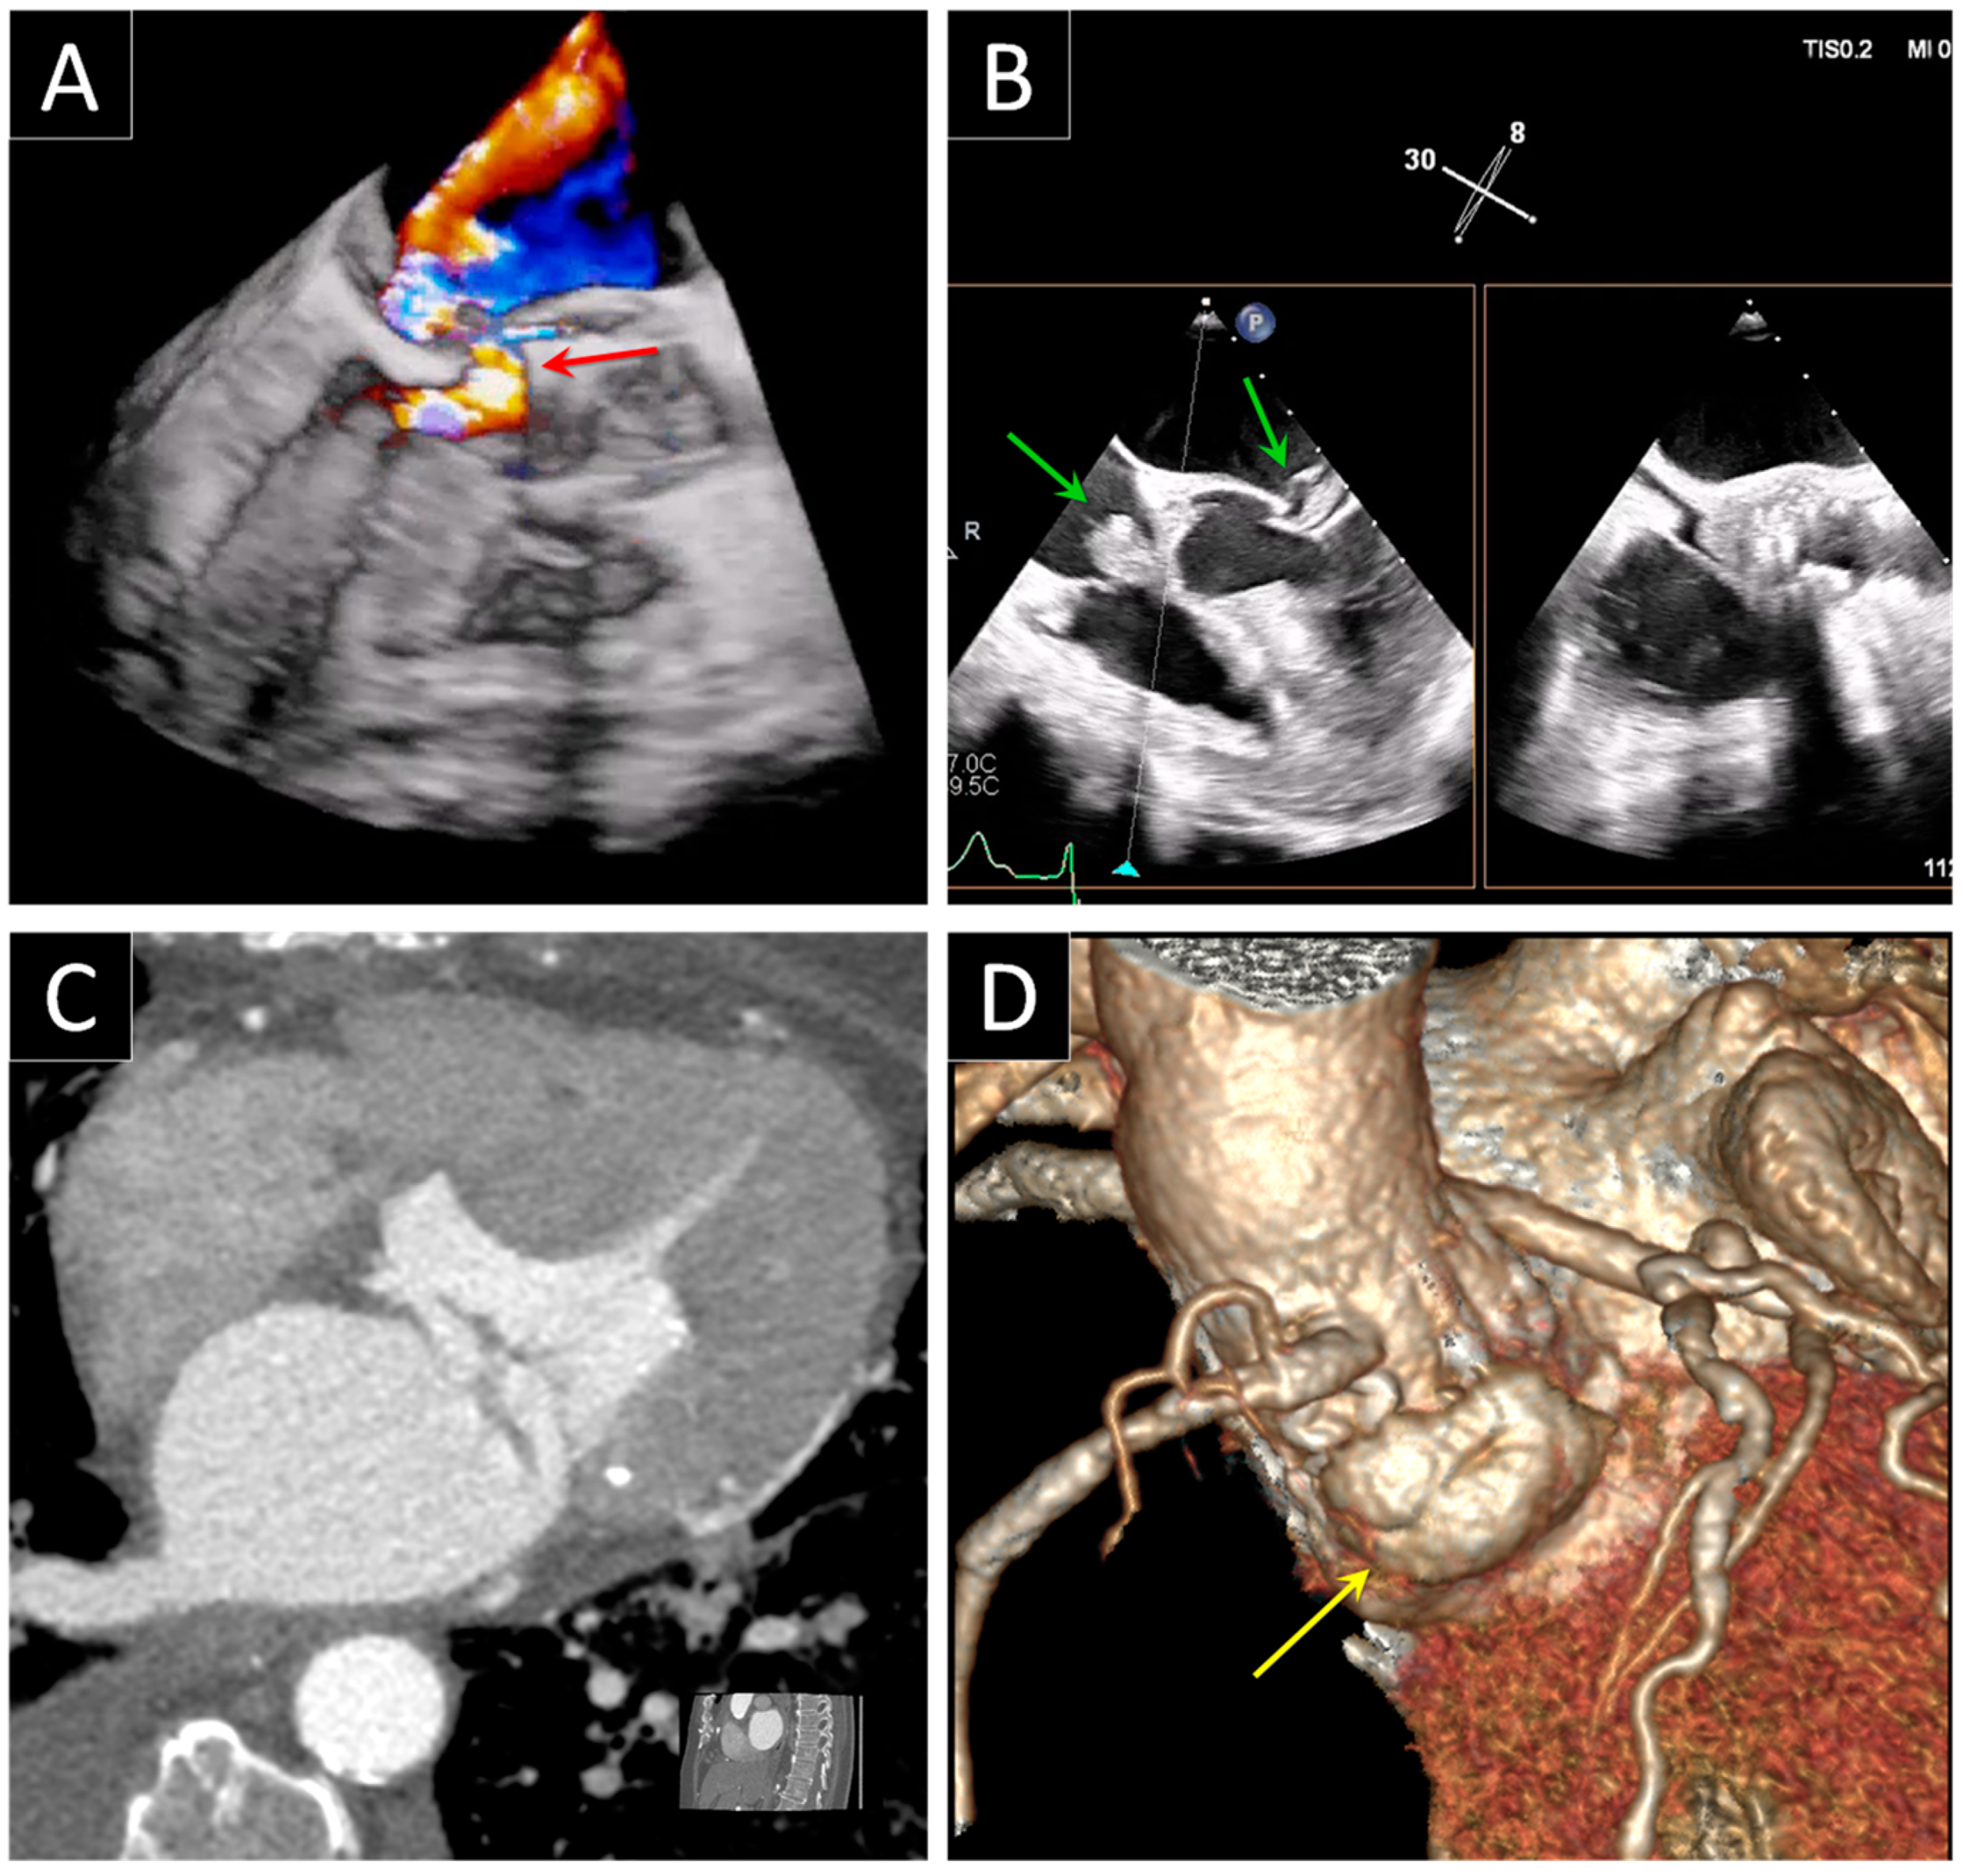

3. Prosthetic Paravalvular Leak

3.1. Mitral Paravalvular Leak

3.2. Aortic Paravalvular Leak